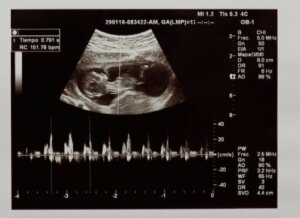

Met hartslag bedoelen we het aantal keren dat het hart samentrekt gedurende één minuut. De hartslag van de foetus is in de eerste weken van de zwangerschap vast te stellen door middel van een echografie of een monitor die we foetale doppler noemen.

Eerst beoordeelt de echoscopist of de hartslag werkelijk aanwezig is, en controleert zo de vitaliteit van de foetus. Daarnaast evalueert de arts hoe vaak het hartje klopt gedurende één minuut. De waarden die men als normaal beschouwt in het foetale stadium liggen tussen 120 en 160 slagen per minuut.